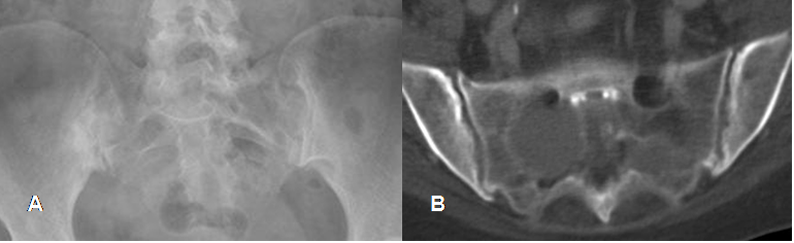

Fig 6. Sacroileitis.

A: Rx AP. Cambios crónicos en SI derecha, con disminución del espacio, erosión y esclerosis.

B: TAC axial. Erosión y esclerosis osea, en el componente iliaco de ambas SI.